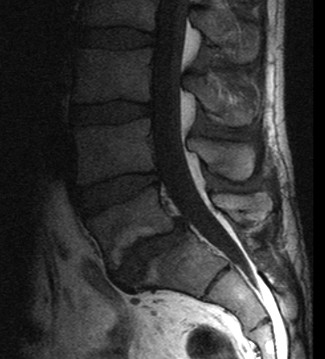

Ich bin 61 Jahre alt und arbeite als Schiffskochbin kräftig gebaut. Im August 2010 wurde ichnach einem Bandscheibenvorfall mit Wirbelgleiten im Bereich L5 -S 1 versteift. Daher kann es zu einer Reizung bzw.

Verhalten bei einer Verstei- fung der Lendenwirbelsäule Klinik für Neurochirurgie Zentrum für Ergo- und Physiotherapie Hinweise für das Verhalten nach Versteifungsoperationen. Die dorsal-dynamische Instrumentierung kann bei bestimmten Krankheitsbildern eine Alternative zur Versteifung darstellen. Die dorsal dynamische Instrumentierung korrigiert Überbeweglichkeiten sie stabilisiert das lockere Bewegungssegment und entlastet somit die Bandscheibe und Facettengelenke ohne die Beweglichkeit des Segmentes ganz aufzuheben. Februar wurde nach einem 3 Bandscheibenvorfall in diesem Segment versteift. Ich bin 61 Jahre alt und arbeite als Schiffskochbin kräftig gebaut. Überlastung der Iliosakralgelenke kommen. Percutaner Spondylodese und Mini-TLIF L5 S1.